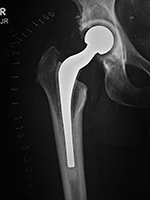

| Metal-on-metal right hip total arthroplasty

Metal-on-metal right hip total arthroplasty |

| 29 year-old woman with bilateral hip dysplasia and placement of right metal-on-metal hip arthroplasty for advanced degenerative arthritis from the hip dysplasia. There is postoperative gas evident as well as a surgical drain. |